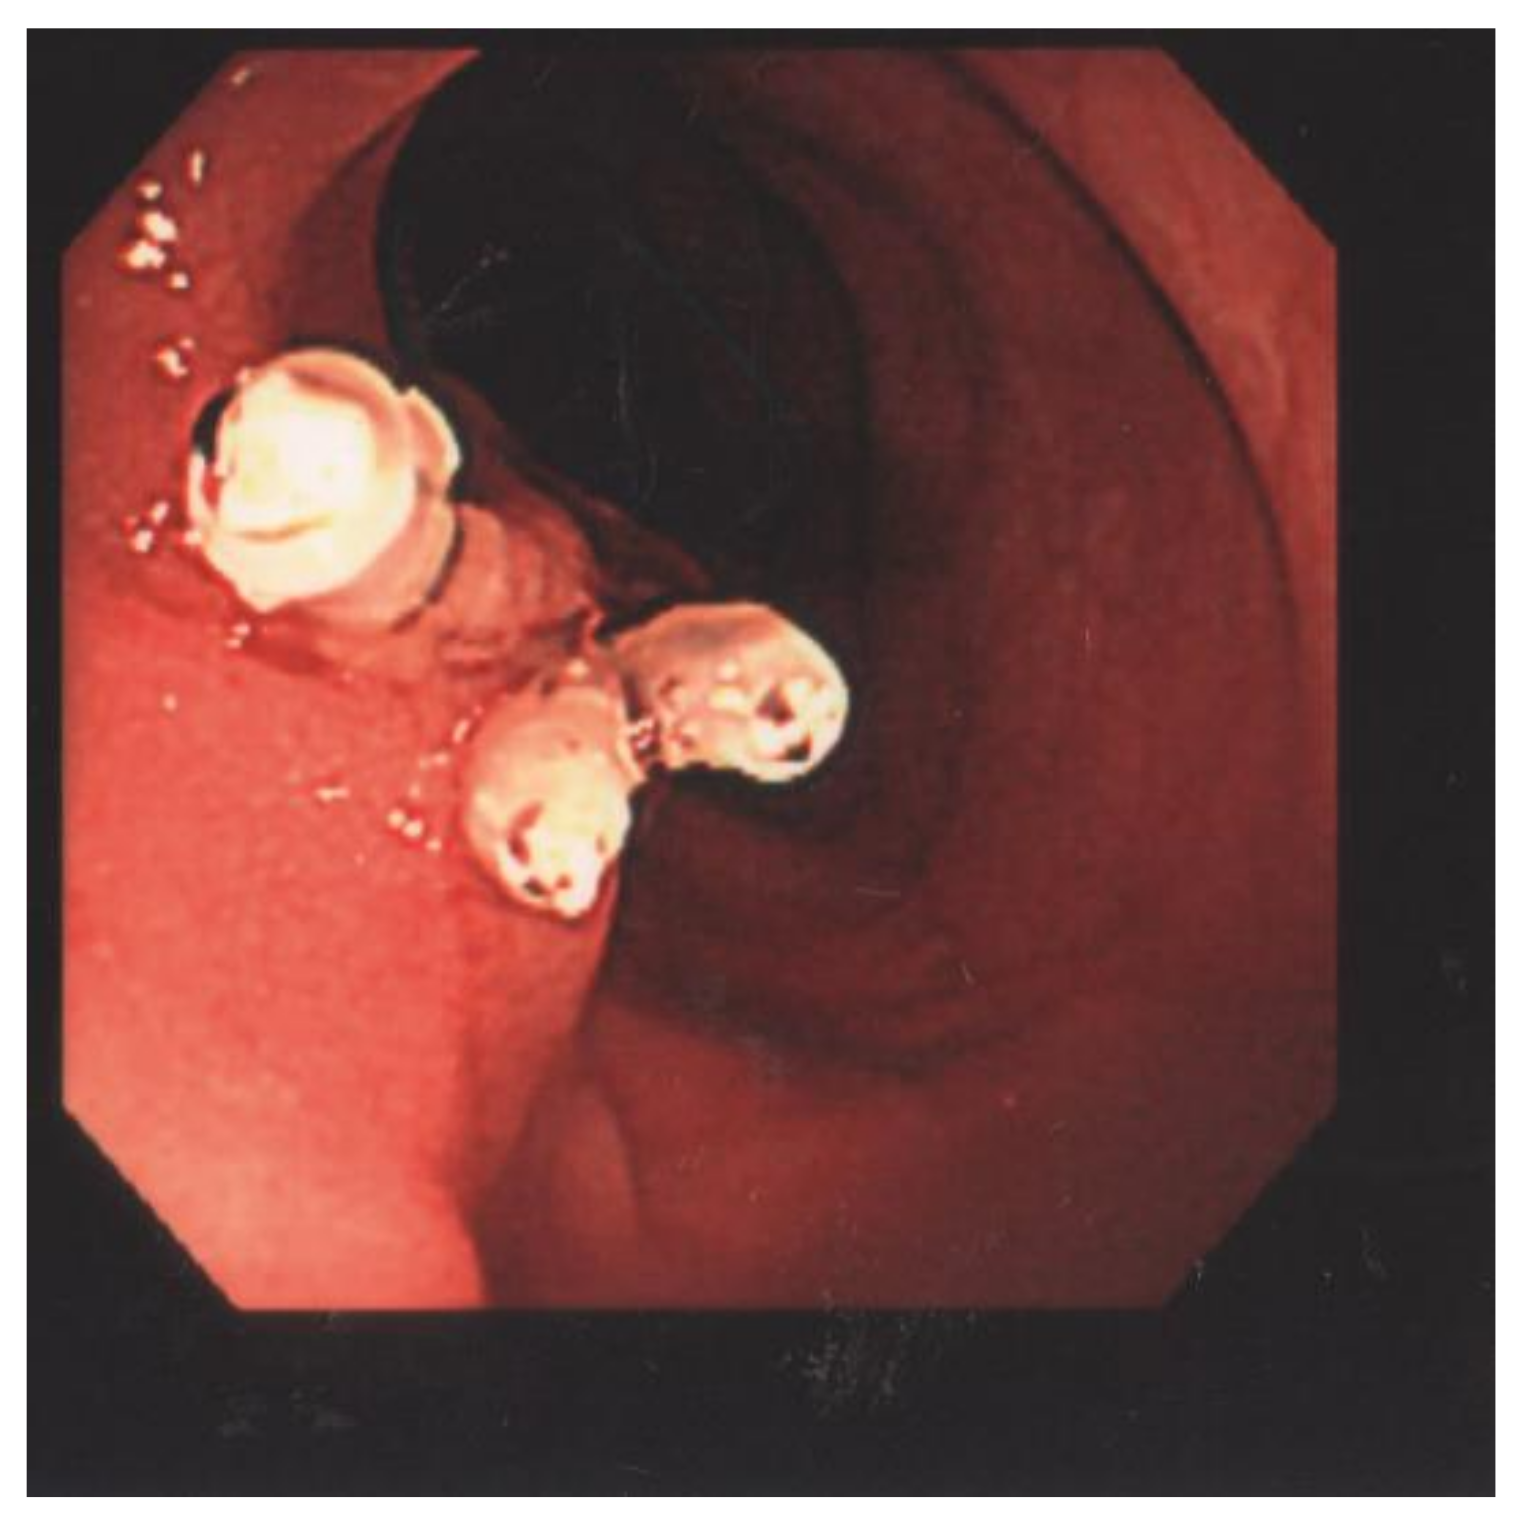

Endoloop-Assisted Polypectomy for a Symptomatic Giant Colonic Polyp in a Pediatric Patient

2. Laboratory Results and Treatment